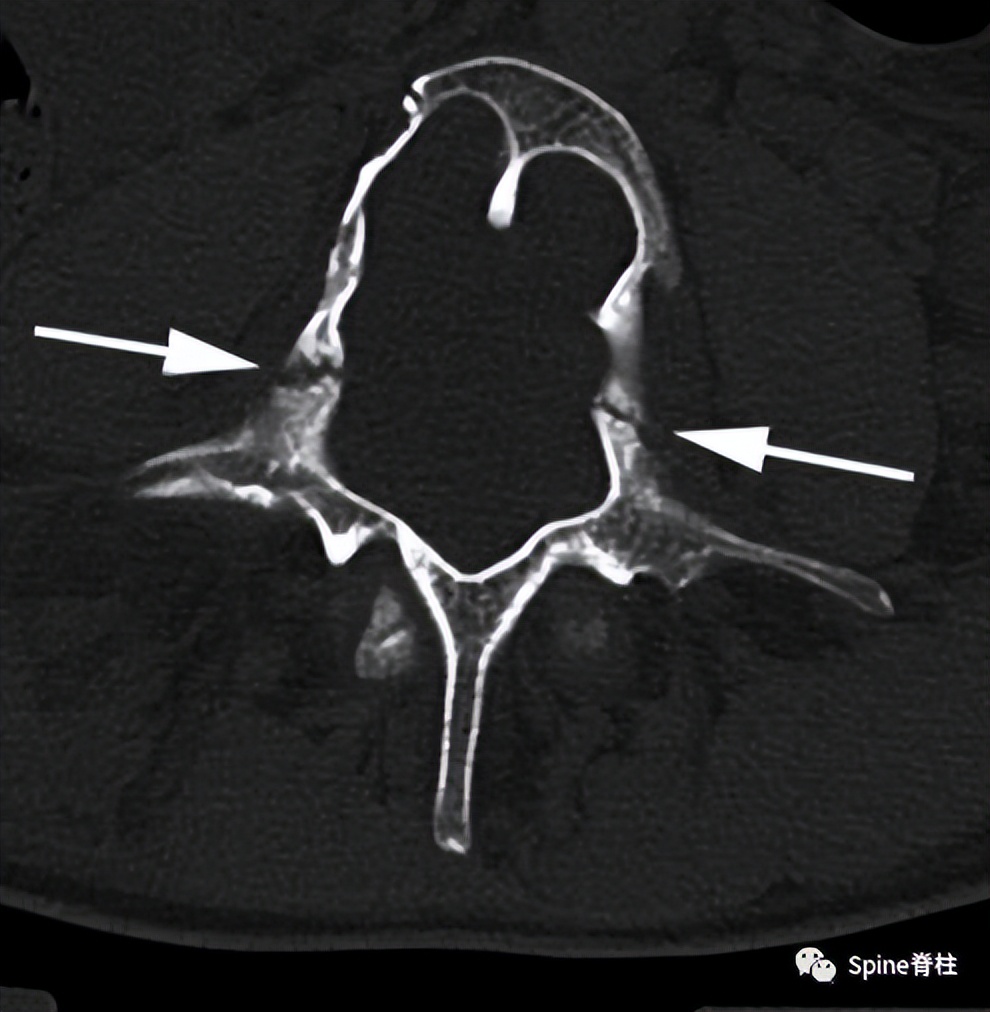

一名20 岁男性1型神经纤维瘤病患者出现背痛和下肢感觉障碍,肌力正常。随后,他出现尿潴留,感觉平面下降至 T10 水平。影像学提示硬膜扩张伴椎体后壁扇形缺损(箭头),L4/5轻度向前滑脱。CT横断面提示腰椎椎弓根拉长变细,双侧椎弓根骨折(箭头)。骨折在 MRI 上显示无水肿信号,提示为慢性骨不连骨折 PMID: 22232056